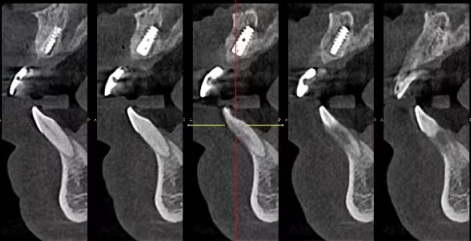

在安装种植牙时,一定要选择正规的医疗机构,找有经验的医生来操作。正规医院的设备更精良,医生的技术也更有保护,这样可以大大提高种植牙的成功几率和使用寿命。